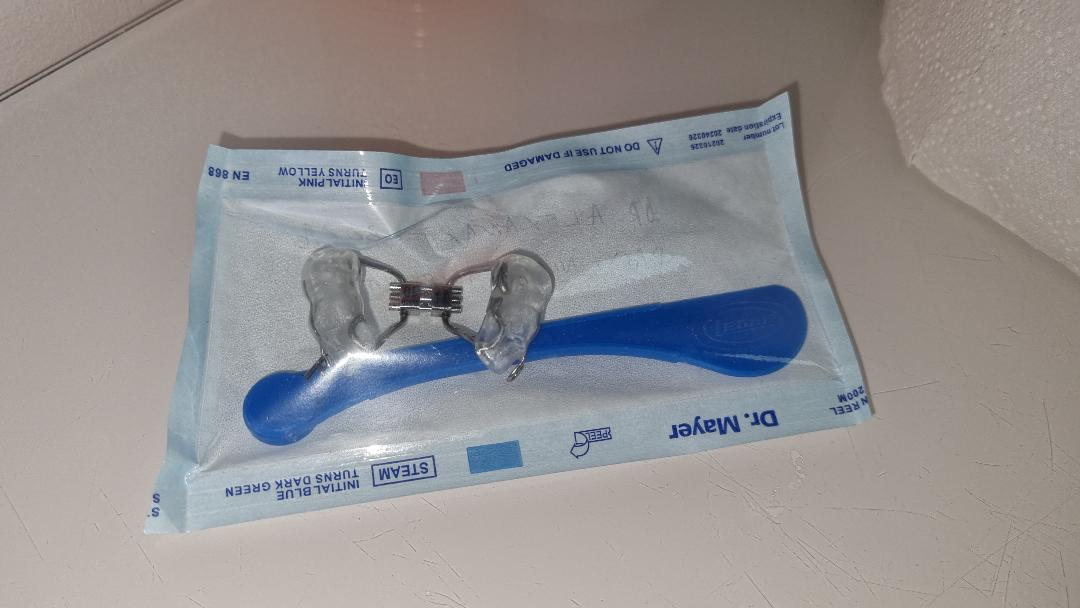

Disjunctoare

Folosirea unui disjunctor maxilar este indicata la copiii la care procesul de crestere a oaselor nu este inca finalizat, si care au maxilare mici, inguste, dinti inghesuiti pe arcada superioara, ocluzie incrucisata sau probleme respiratorii.

Disjunctoare hibride

Disjunctor ancorat pe miniimplanturi.

Este utilizat in cazurile nechirurgicale si non-extractionale pentru marirea maxilarului superior.